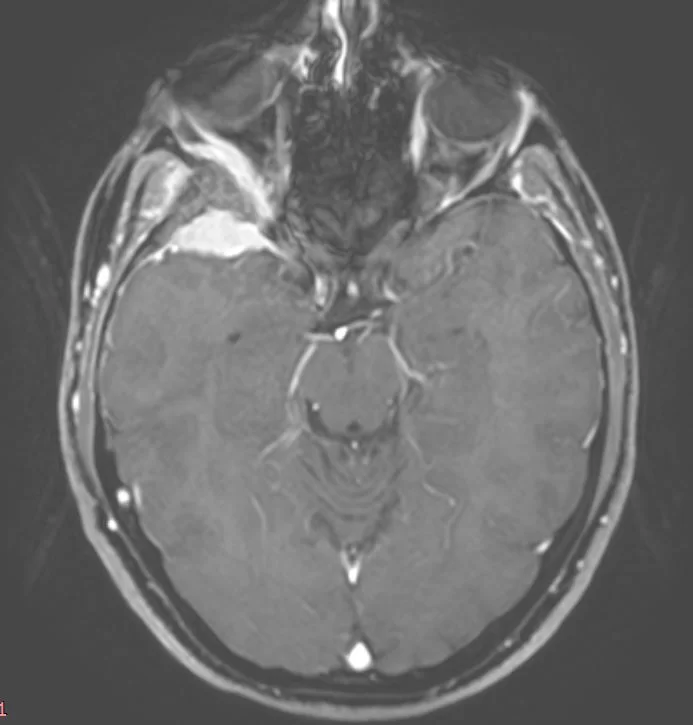

Ευμεγεθες Ακουστικό Νευρίνωμα με πίεση επί του εγκεφαλικού στελέχους

Ασθενής άνδρας, 48 ετών με συμπτώματα εμέτου και αδυναμίας από 15ημέρου περίπου. Στην αντικειμενική εξέταση διαπιστώθηκε σημαντική πάρεση προσωπικού νεύρου αριστερά και αστάθεια βάδισης &